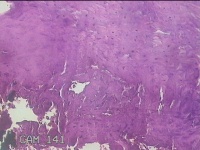

左大拇指红色赘生物

性别

男

年龄

75岁

临床诊断

病毒性疣?

一般病史

灰白粉红色肿物0.5x0.3x0.2cm一个,表面糜烂。

标本名称

大体所见

左大拇指起红色赘生物1年。

不具诊断价值。

皮角